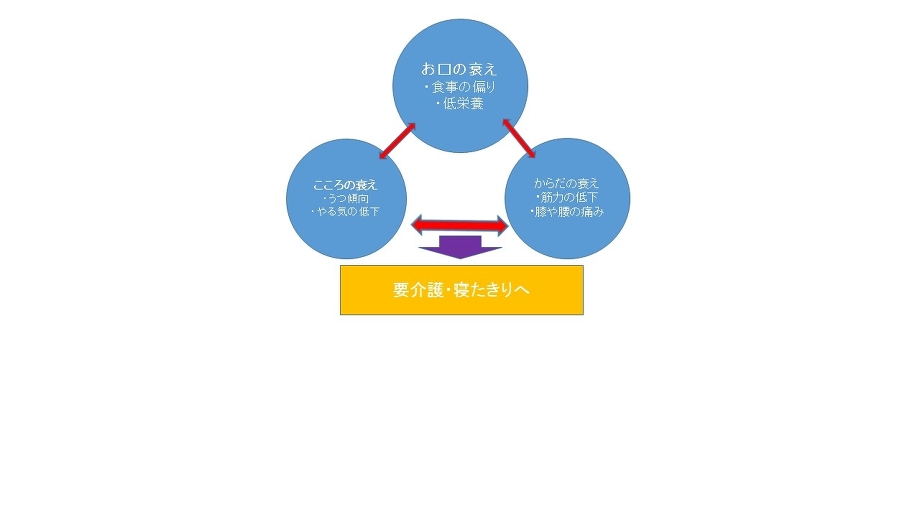

秋は涼しくなって過ごしやすい季節ですが、夏の間にたまった疲れが目に見えて現れ始めるのが実は秋なのです。夏バテが長期化、深刻化することで、自律神経が乱れ、不調を起こしやすくなります。

夏の間に冷たいものを摂りすぎたり、冷房によってカラダが冷やされると、疲れやだるさ・肩こりや腰痛などが起こりやすくなります。また、季節の変わり目で風邪もひきやすく、精神的にも落ち込みやすいので、秋の食材でカラダを温めながら免疫力をアップし、ココロもカラダも元気を取り戻しましょう!